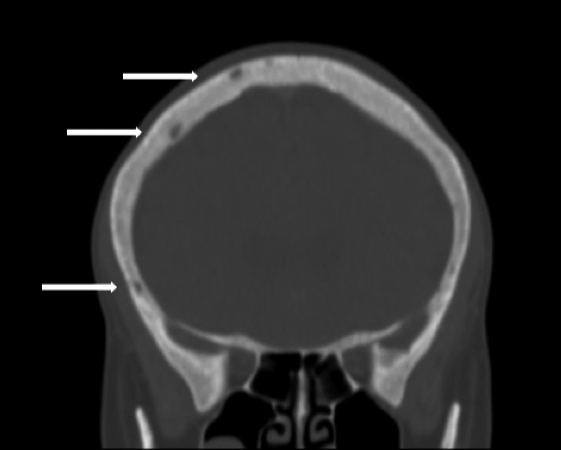

Tiroides aumentada de tamaño a expensas del lóbulo derecho, múltiples formaciones nodulares, siendo la mayor con degeneración quística de 23x15mm. No adenomegalias (Figura 5); c) TAC de cerebro (con cte): Aumento difuso de la densidad ósea con múltiples lesiones osteolíticas en sacabocado (Figura 6); d) Proteinograma por EF: leve aumento en zona de alfa-2 globulina. e) Marcador tumoral (mama) CA 15,3:7,6 U/ml + examen ginecológico, ambos normales. f) Centellograma óseo total marcado con Tc 99: múltiples lesiones osteolíticas (Figura 7); g) Centellograma de paratiroides marcado con Sestamibi: captación selectiva en ambos polos inferiores sugestiva de tejido paratiroideo hiperplasiado. (Figura 8)